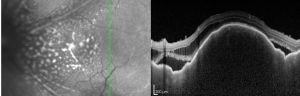

As outlined above in the ‘Diagnostic Studies’ section, evaluation of uveal lymphoma includes ultrasonography, angiography and high resolution neuroimaging. B-scan ultrasonography allows for evaluation of the posterior segment of the eye. Findings are not specific, but can aid in narrowing the differential diagnosis and identifying ESE.[18] OCT imaging can also be beneficial in diagnosis and often reveals a lumpy bumpy choroid as seen in image 4.

Angiography can help to localize the layer that the infiltrates reside and can show hypofluorescent areas due to the blocking effect of sub-RPE masses. If RPE atrophy has occurred, hyperfluorescent areas may be seen.[19] It has been noted that ICG is the preferred form of angiography for uveal lymphoma over fluorescein angiography (FA) as ICG yields more reproducible findings.[1][20]